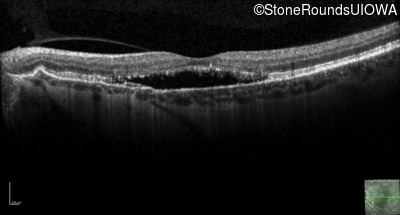

Age at visit: 57 years